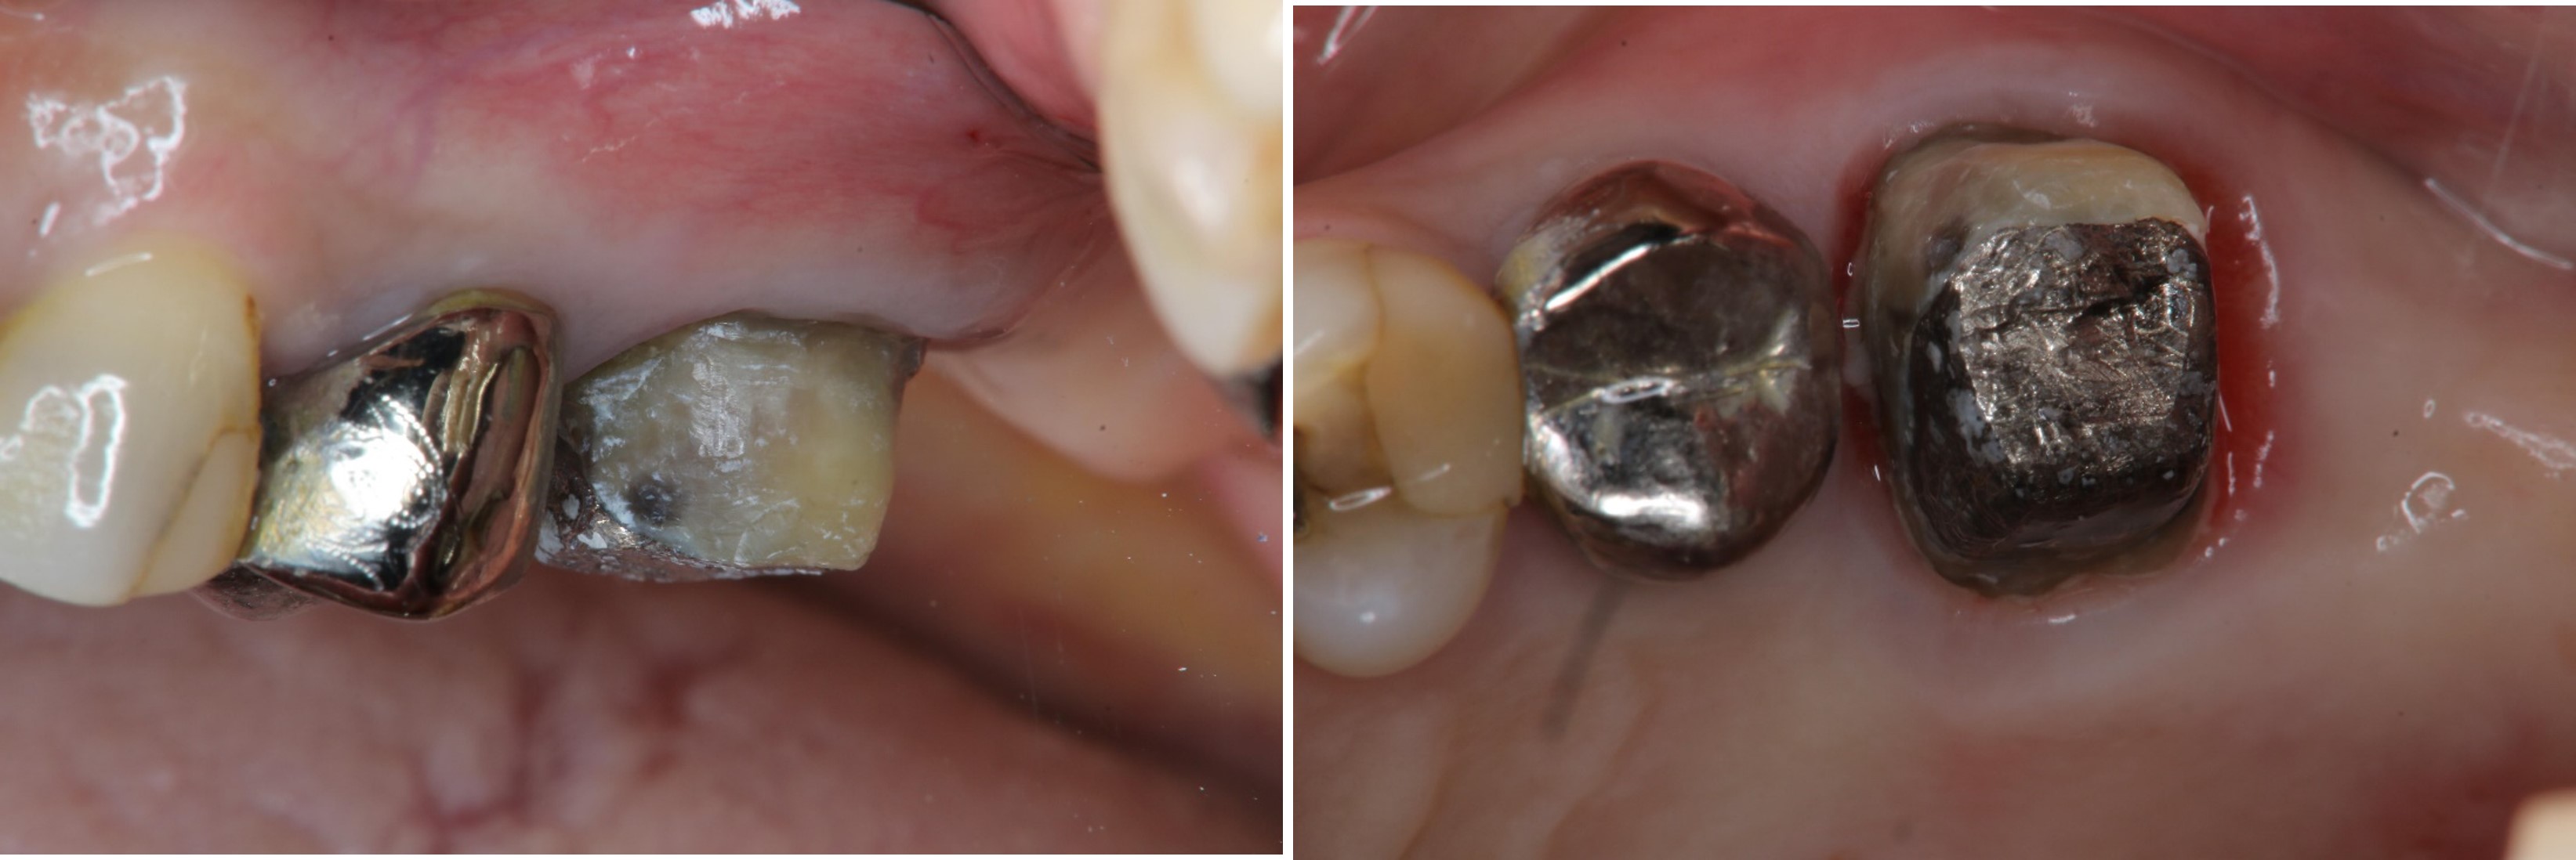

鑄造金屬釘柱

膺復前評估牙齦、牙齒狀態